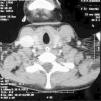

Niña de 12 años, previamente sana, que acude a urgencias por fiebre, dificultad respiratoria y dolor torácico. Refería cuadro febril de 5 días de evolución, rinorrea, tos y odinofagia en tratamiento con paracetamol y diclofenaco. Exploración: palidez mucocutánea, taquicárdica, no soplos; polipnea basal, con tiraje subcostal, hipoventilación basal. Hiperemia faríngea con punteado en amígdala derecha. Resto normal. En la radiografía de tórax inicial se observa un patrón alveolar bilateral compatible con neumonía intersticial iniciándose tratamiento con vancomicina, cefotaxima y eritromicina. Analítica al ingreso: hemograma: leucocitos 23.930/μl, Hb 10,6 g/dl, plaquetas 44.000/μl, creatinina 2,4 mg/dl, urea 222 mg/dl. A las pocas horas del ingreso se decide traslado a UCIP por aumento de la dificultad respiratoria e insuficiencia renal oligúrica. Allí se inicia ventilación mecánica no invasiva mejorando clínicamente. En el segundo día de ingreso crece en hemocultivo Fusobacterium y estreptococo, iniciándose tratamiento con meropenem y clindamicina. La paciente no presentaba datos externos sugestivos de trombosis de la vena yugular interna (eritema, empastamiento o dolor cervical). Tras conocer la etiología microbiológica, se sospecho síndrome de Lemierre, solicitándose TC cérvico-torácica (fig. 1) que demostró la existencias de lesiones nodulares múltiples cavitadas de predominio periférico (abscesos pulmonares sépticos) y defecto de repleción en relación a trombosis de vena yugular interna (fig. 2), confirmándose el diagnóstico de sospecha. Se inició tratamiento anticoagulante con heparina de bajo peso molecular. Clínicamente la paciente presentó un fallo hipoxémico progresivo severo (PaO2/FiO2 mínima de 184 y PaO2 mínimas de 55 mmHg), manejándose en todo momento sin necesidad de ventilación invasiva. Presentó una pogresiva mejoría respiratoria pudiéndose retirar la ventilación no invasiva a los 3 días y la oxigenoterapia 10 días después. Al octavo día presentó derrames pleurales bilaterales que precisan colocación de tubos pleurales. Recibió tratamiento antibiótico durante 6 semanas (3 semanas con imipenem y 3 semanas oral con amoxicilina-ácido clavulánico) y tratamiento anticoagulante durante 3 meses (el estudio de trombofilia fue normal). Al alta la paciente se encontraba asintomática.

Figura 1. Lesiones nodulares pulmonares múltiples compatibles con accesos pulmonares.